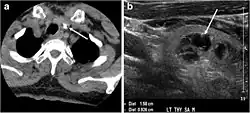

- Fig. 7. A 51-year-old female patient post total thyroidectomy for PTC with elevated thyroglobulin measurement. an Axial non-enhanced CT scan of the neck at the level of the thyroid bed demonstrates a well-defined, rounded, homogenously dense soft tissue situated between the trachea and left internal jugular vein (white arrow). b Transverse ultrasound image of the neck demonstrates a well-defined, homogeneous, hypoechoic soft tissue nodule measuring 6 mm (white arrow) with no detected micro-calcifications. Biopsy showed a predominantly residual normal thyroid tissue with micro-foci of PTC.[1]